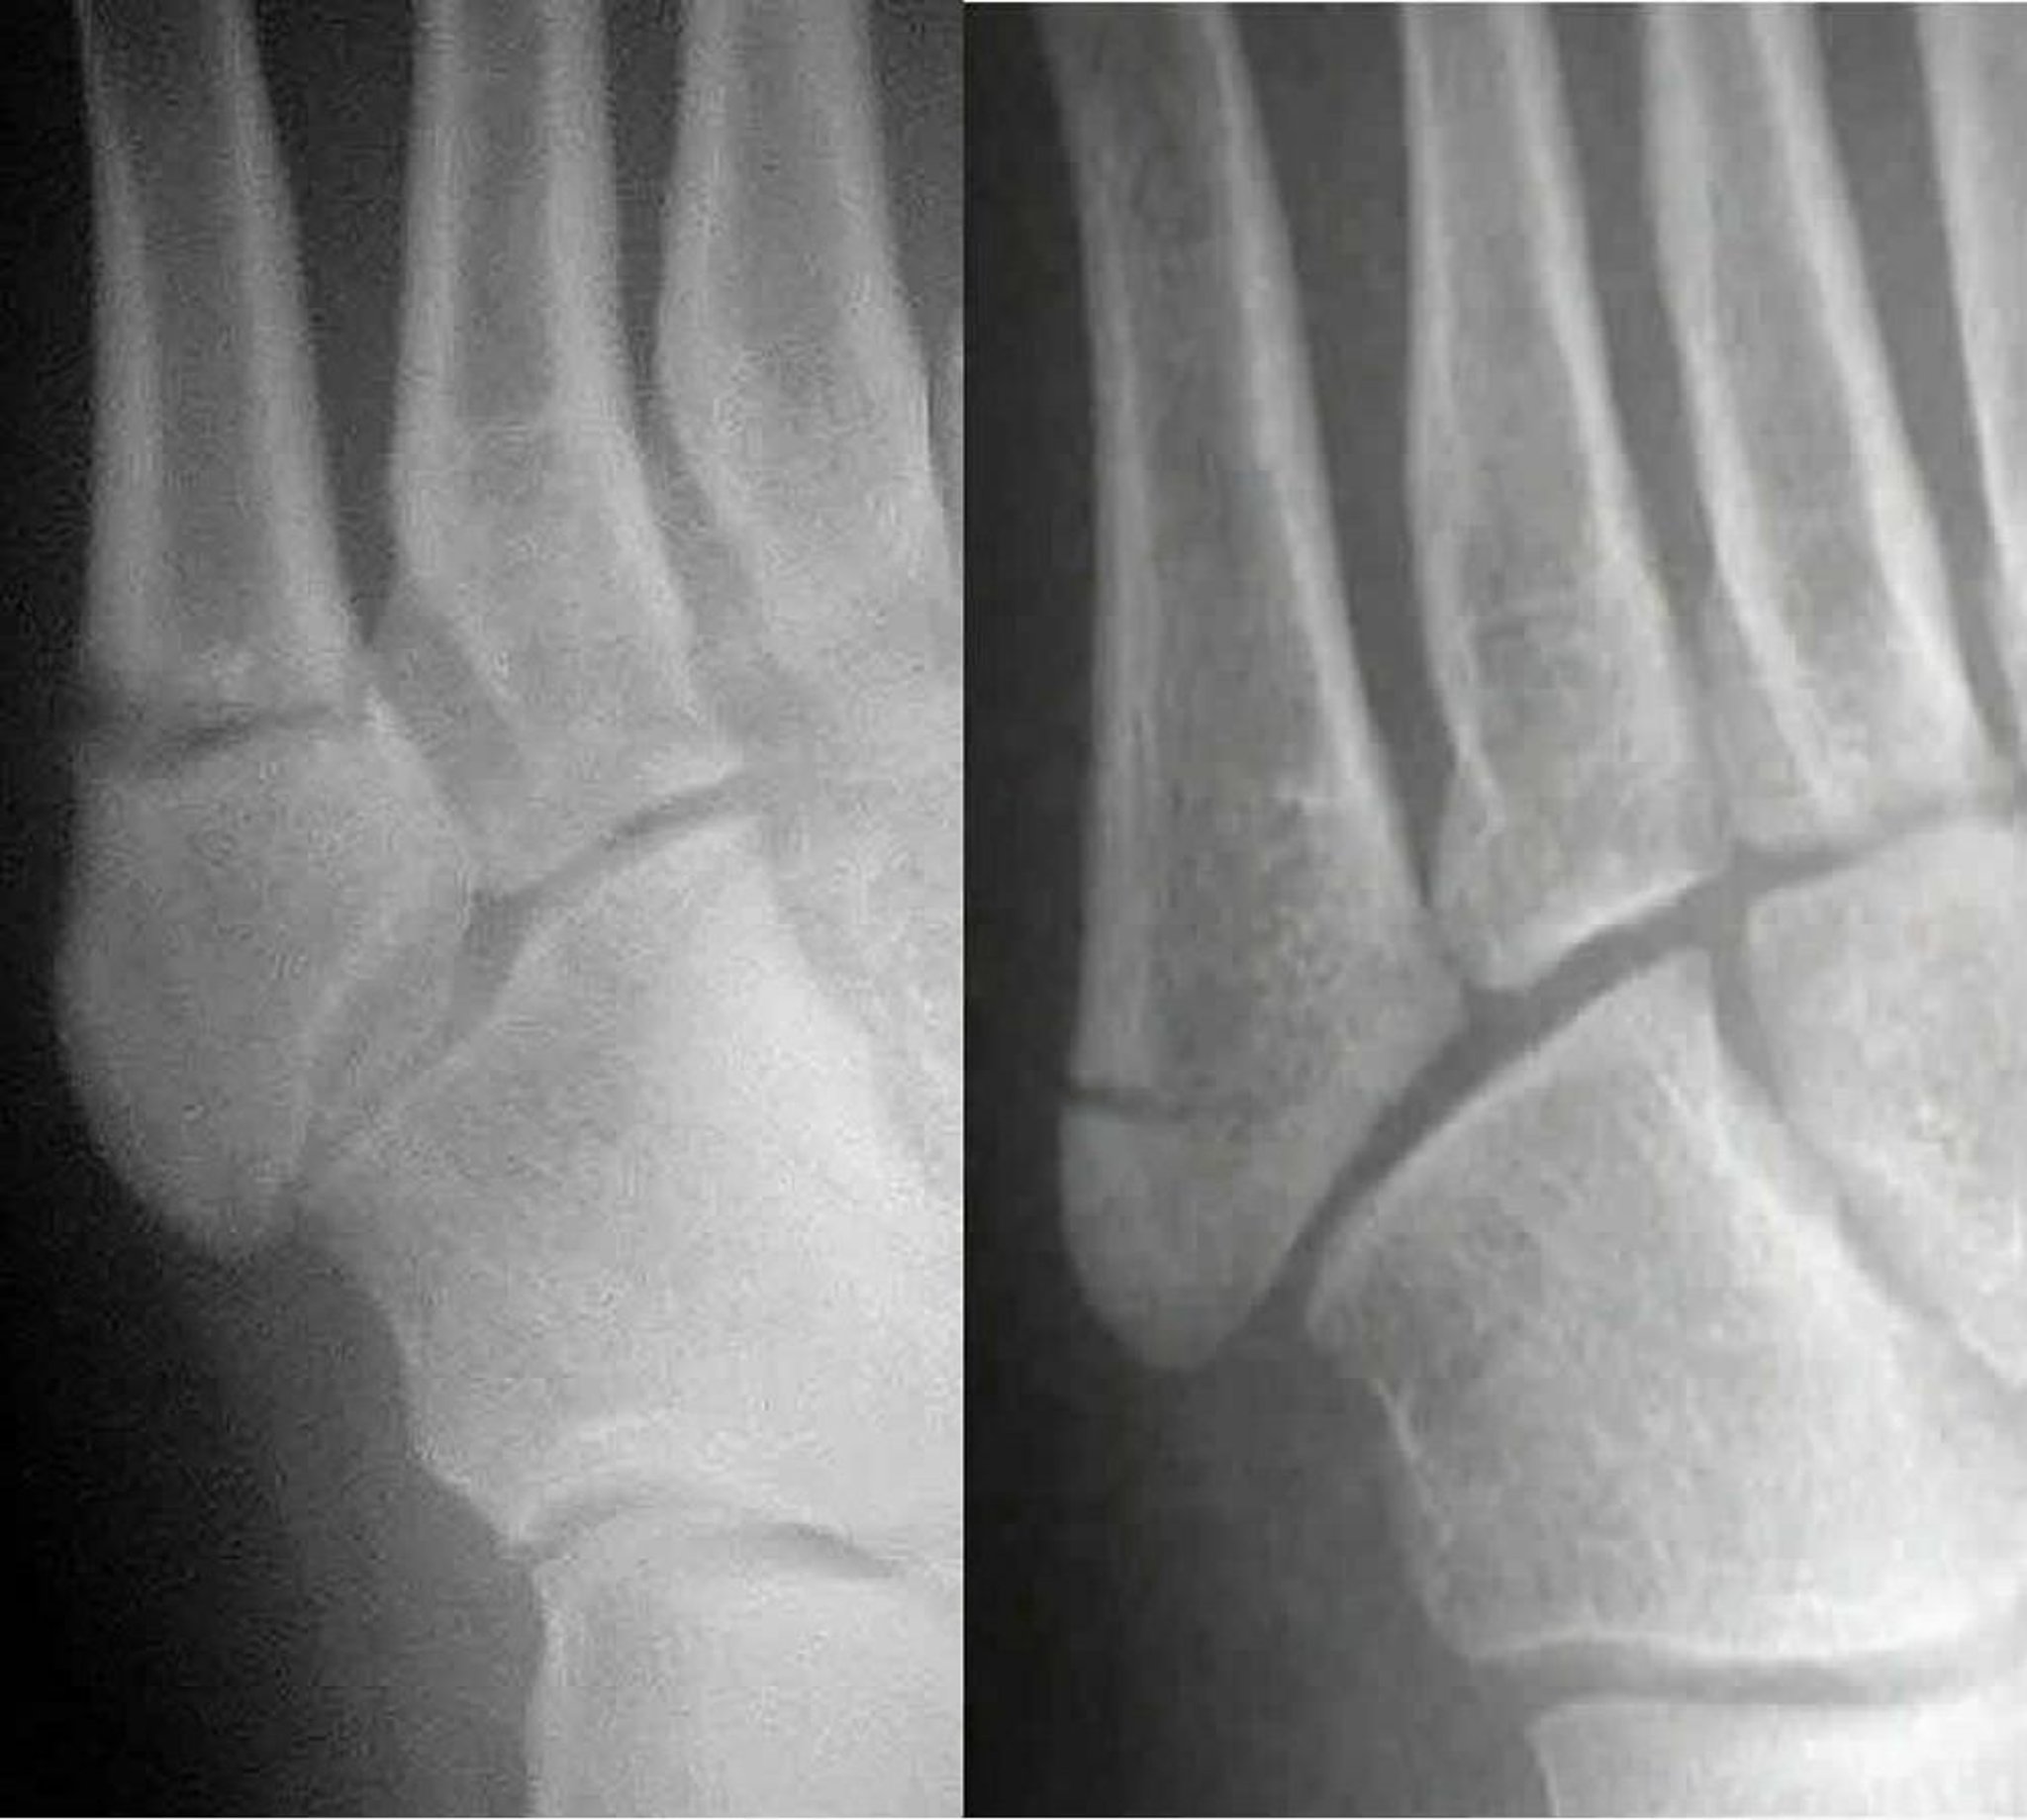

Jones- und Pseudo-Jones-Frakturen

Bei einer Jones-Fraktur (links) ist der Schaft des 5. Mittelfußknochens betroffen; bei einer Pseudo-Jones-Fraktur (rechts) ist die Basis des 5. Mittelfußknochens betroffen. Es ist wichtig, die beiden zu unterscheiden, weil sie unterschiedlich behandelt werden.

Images courtesy of Danielle Campagne, MD.